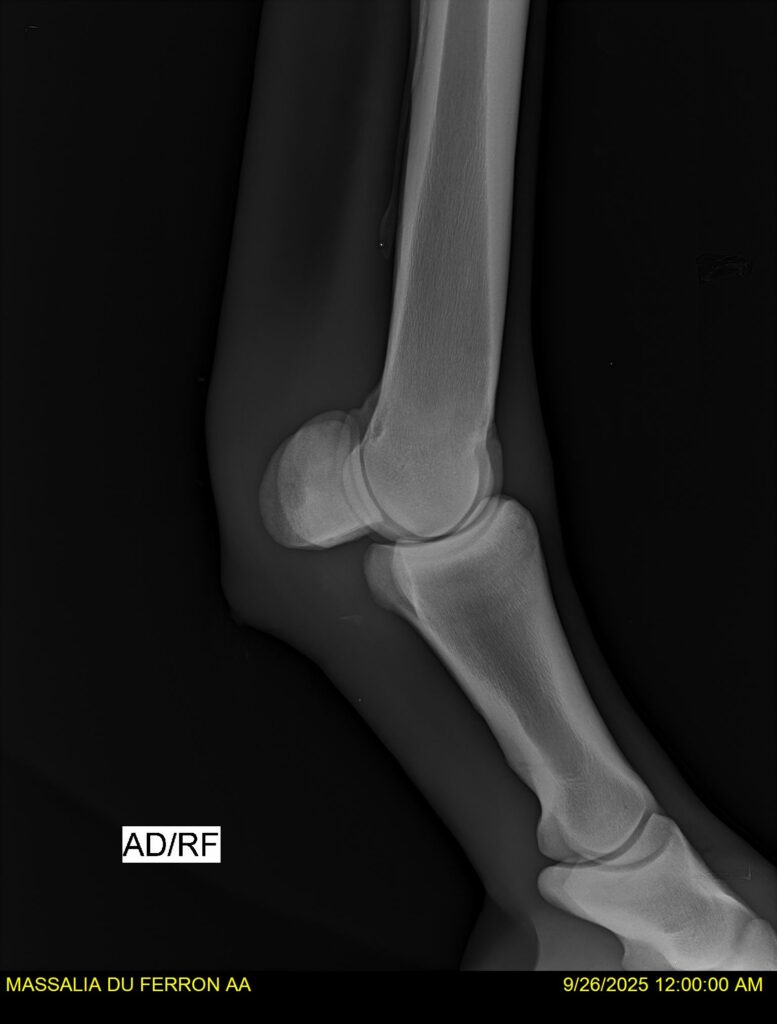

MASSALIA DU FERRON, jument qui prendra 4 ans par PRESTIGE KALONE x TRESOR DU RENOM. Un mental en or et un véritable sens de la barre ! Facile d’accès ! Bonne énergie et bons moyens. Souche moderne et très intéressante. Transport OK, maréchalerie OK, santé RAS, Bilan clichés radios OK.

RADIOS et COMPTE RENDU